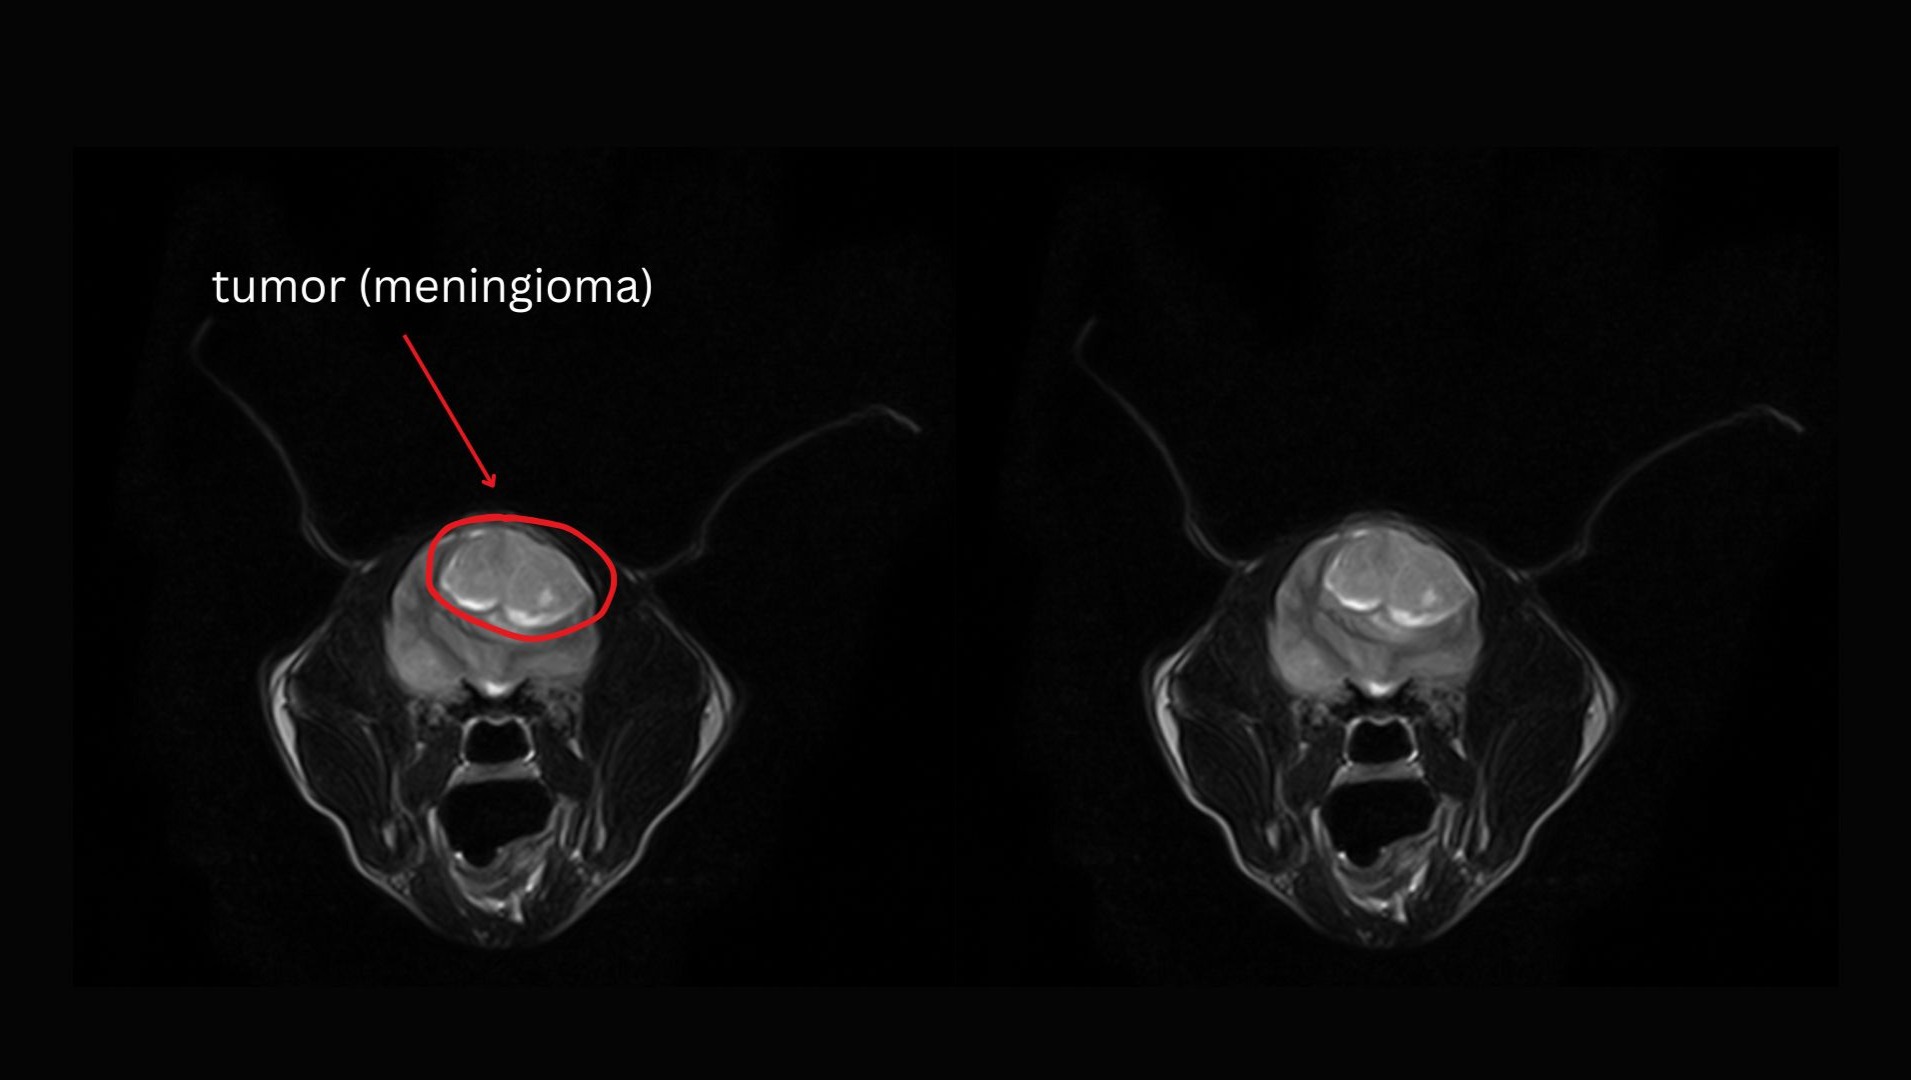

On October 30, we took Wendy to Remedy, where she underwent anesthesia and an MRI scan, which revealed a large meningioma that was putting immense pressure on her brain. Dr. Mona Qahwash, the neurologist, expressed her concern that, without surgery, "Wendy could pass away at any moment", as the tumor could begin to interfere with vital reflexes, including her ability to breathe.

Wendy's MRI's: